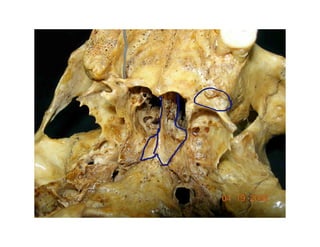

Este documento describe los principios de construcción de la arquitectura craneofacial, incluyendo el metamerismo, la simetría y la paquimería. Explica la organización peri-cavitaria del cráneo a través de columnas y vigas, y analiza las diferentes fascias profundas del cuello. También destaca la importancia de conocer la irrigación ósea con orientación quirúrgica, mencionando los principales aportes vasculares y suplementarios así como el origen, trayecto y retorno venoso de la carót